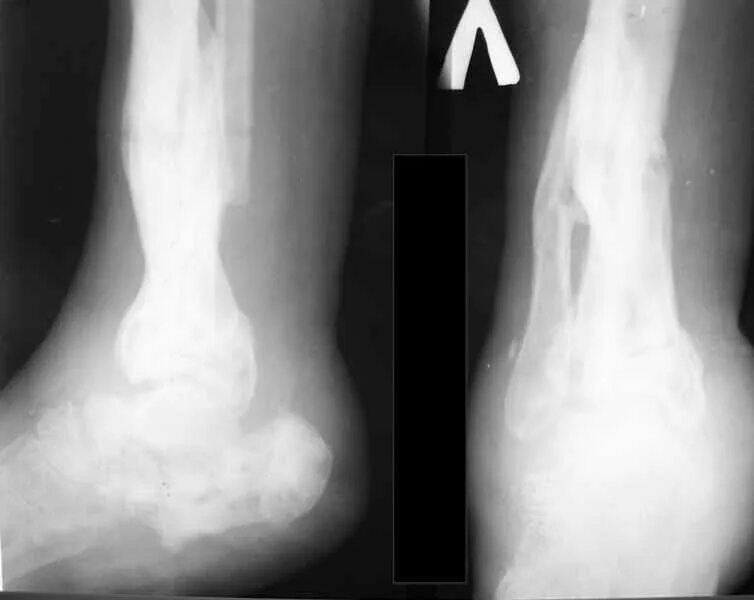

Пяточный перелом без смещения